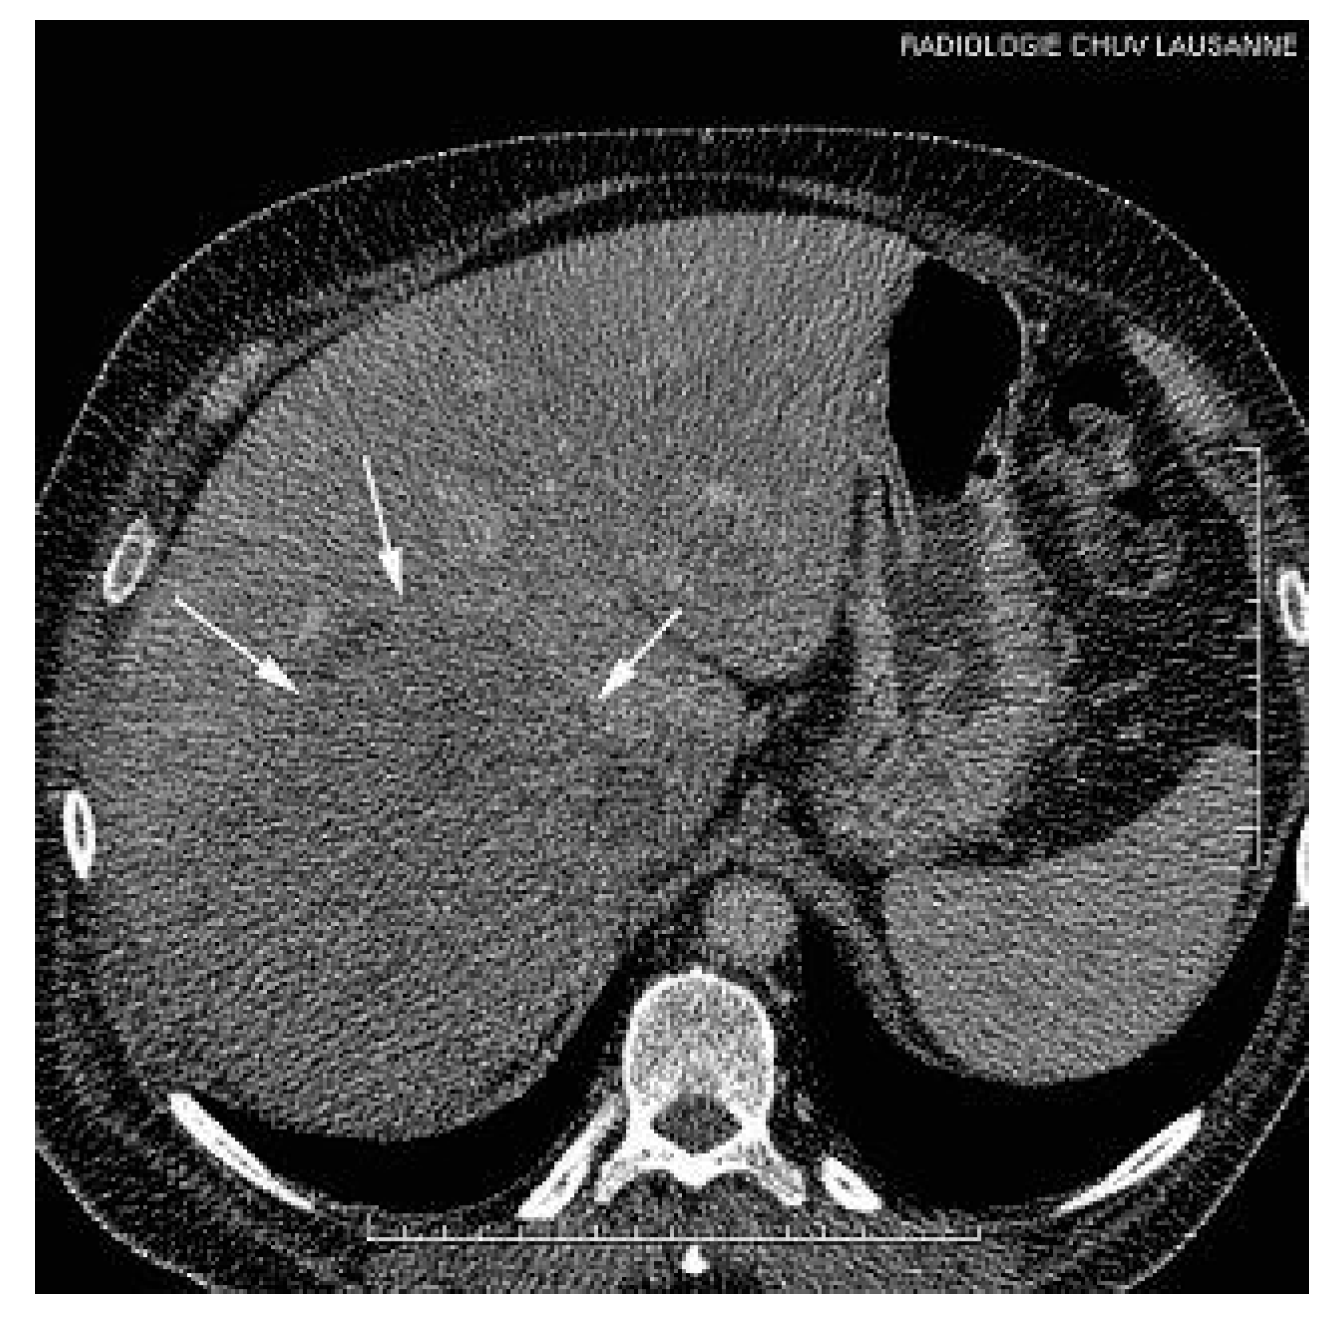

A thoraco-abdominal computed tomography (CT) scan showed the presence of a huge right hepatic mass with extension into the IVC and the RA (Figure 2 and Figure 3).

Figure 2. Abdominal CT. A huge hepatic mass involving almost the whole right liver (arrows).